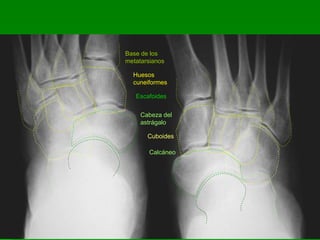

Base de los

metatarsianos

Huesos

cuneiformes

Escafoides

Cabeza del

astrágalo

Cuboides

Calcáneo